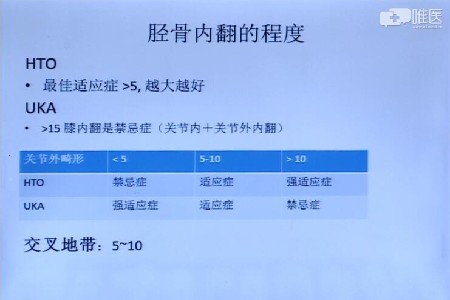

牛津单髁置换手术的主要适应症 网易订阅

牛津单髁置换手术的主要适应症 网易订阅

牛津单髁置换手术的主要适应症 网易订阅

膝关节内侧单髁置换的临床要点 金约应医疗

张清港 Oxford膝关节内侧单髁置换 健康频道 手机搜狐